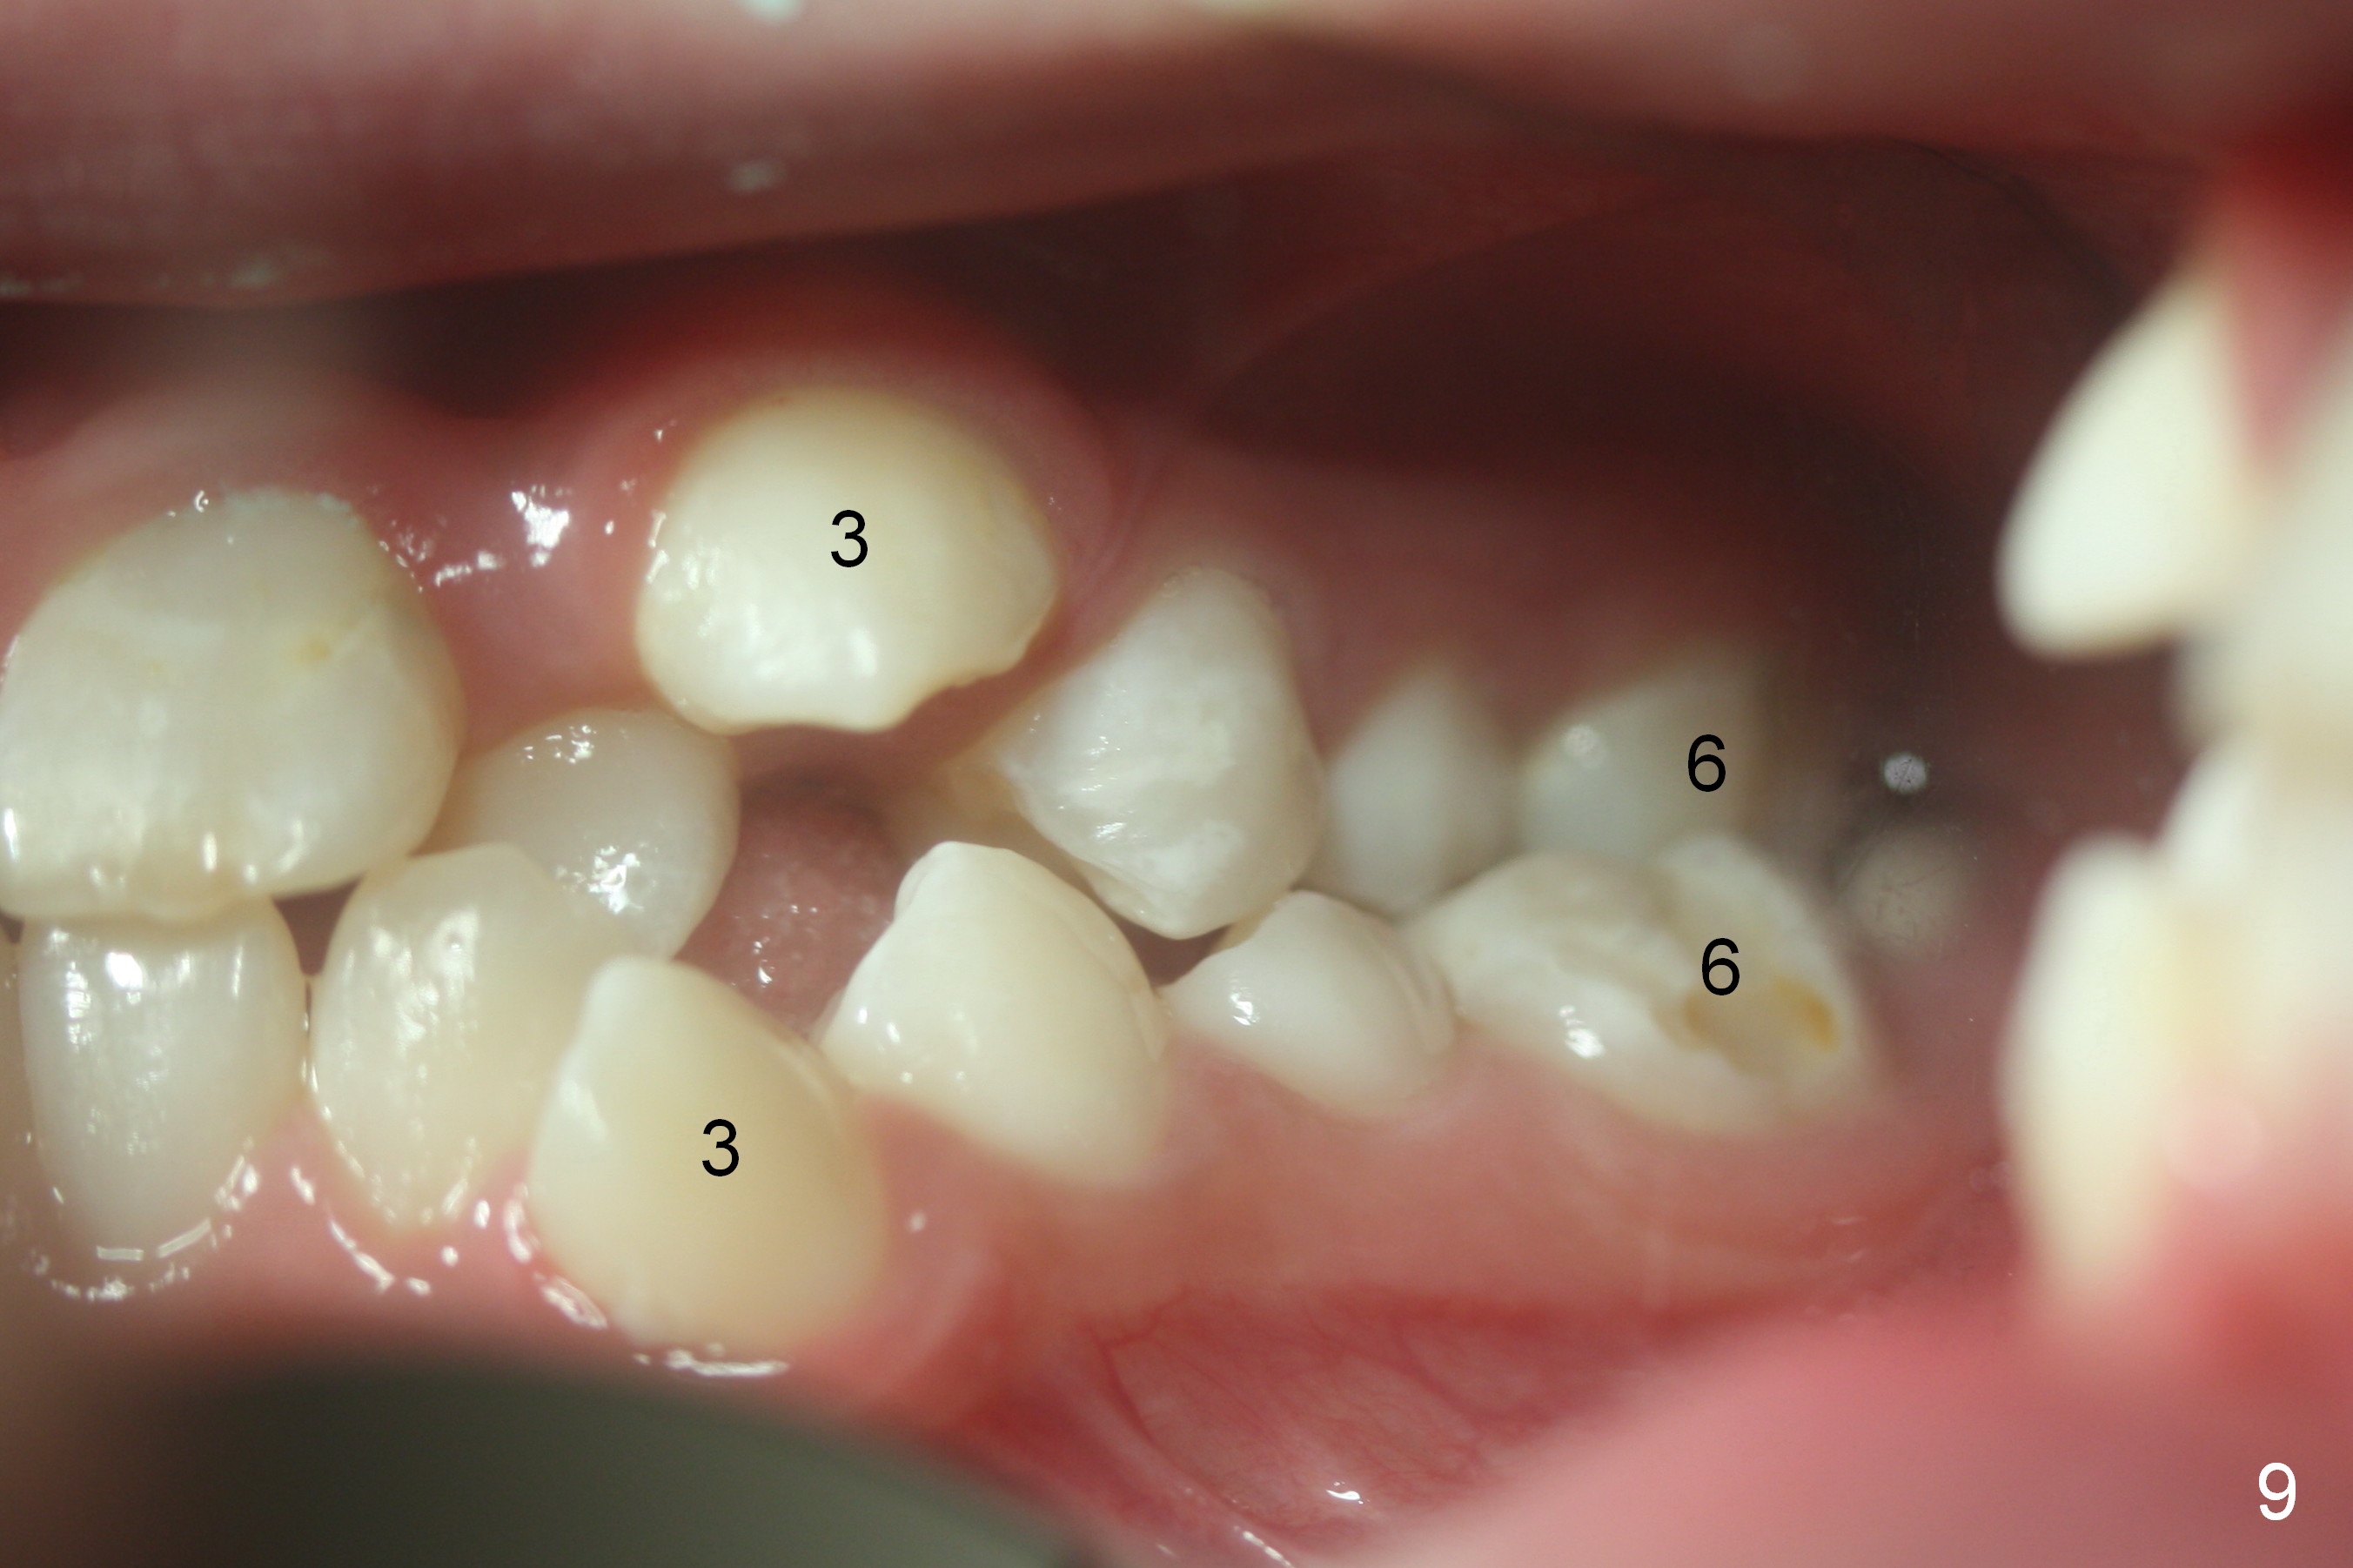

Cross bite also exists at 6s (Fig.9,11). Place molar bands with sheets with the upper ones (potentially for palatal expander), with cleats with the lower ones (possibly for elastics).

The right canines are blocked (Fig.6,9). Use an elastic between them as early as possible to facilitate eruption, which is not done immediately post banding and extraction of R4s (Fig.12 (.014' niti wires)).